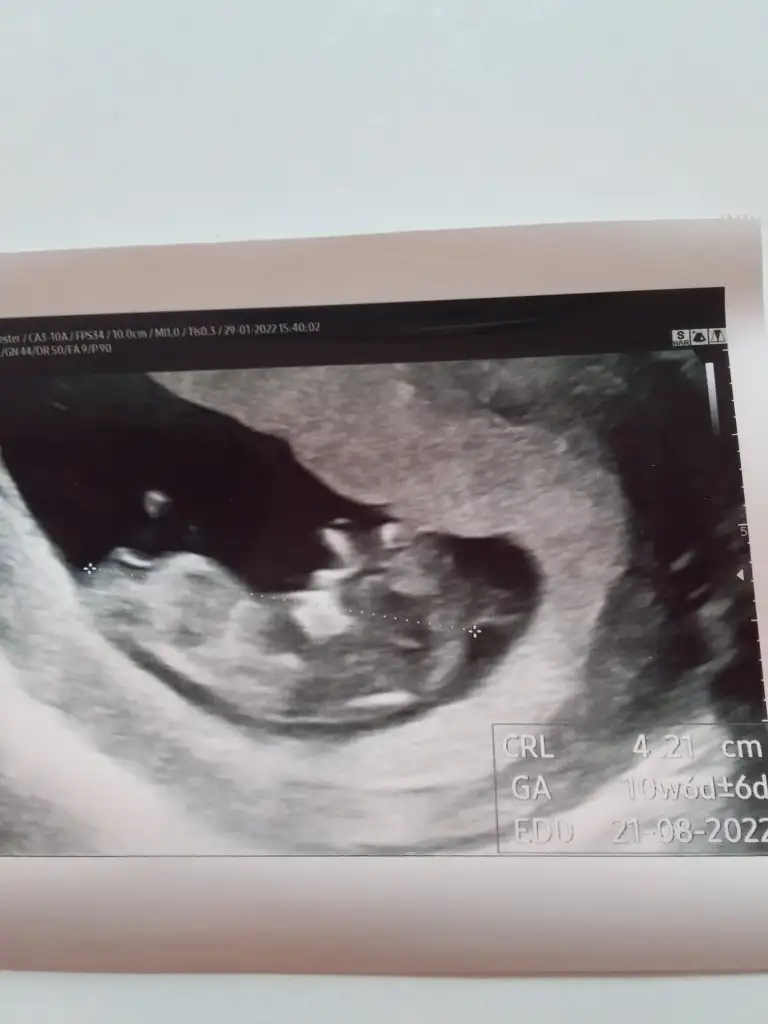

Merhaba gözünüz aydın , kanamalarıniz ne sıklıkla oluyor aceba,birde kalp atışından sonra hangi ilaçlara devam ediyorsunuz hala şuan içinGunaydin kızlar. Dün kontrolümüz vardi. 10+6 olmus bebisimiz. Kanama alanı cok az kalmıs. 15 gün sonraya cagırdı ense kalınlıgi ve ikili test icin. 15 gün sonra sende normal hamileler gibi olcaksın bütün ilacların bırakcaz normal hamilelirin kullandıgı ilaclara baslıcan dedi